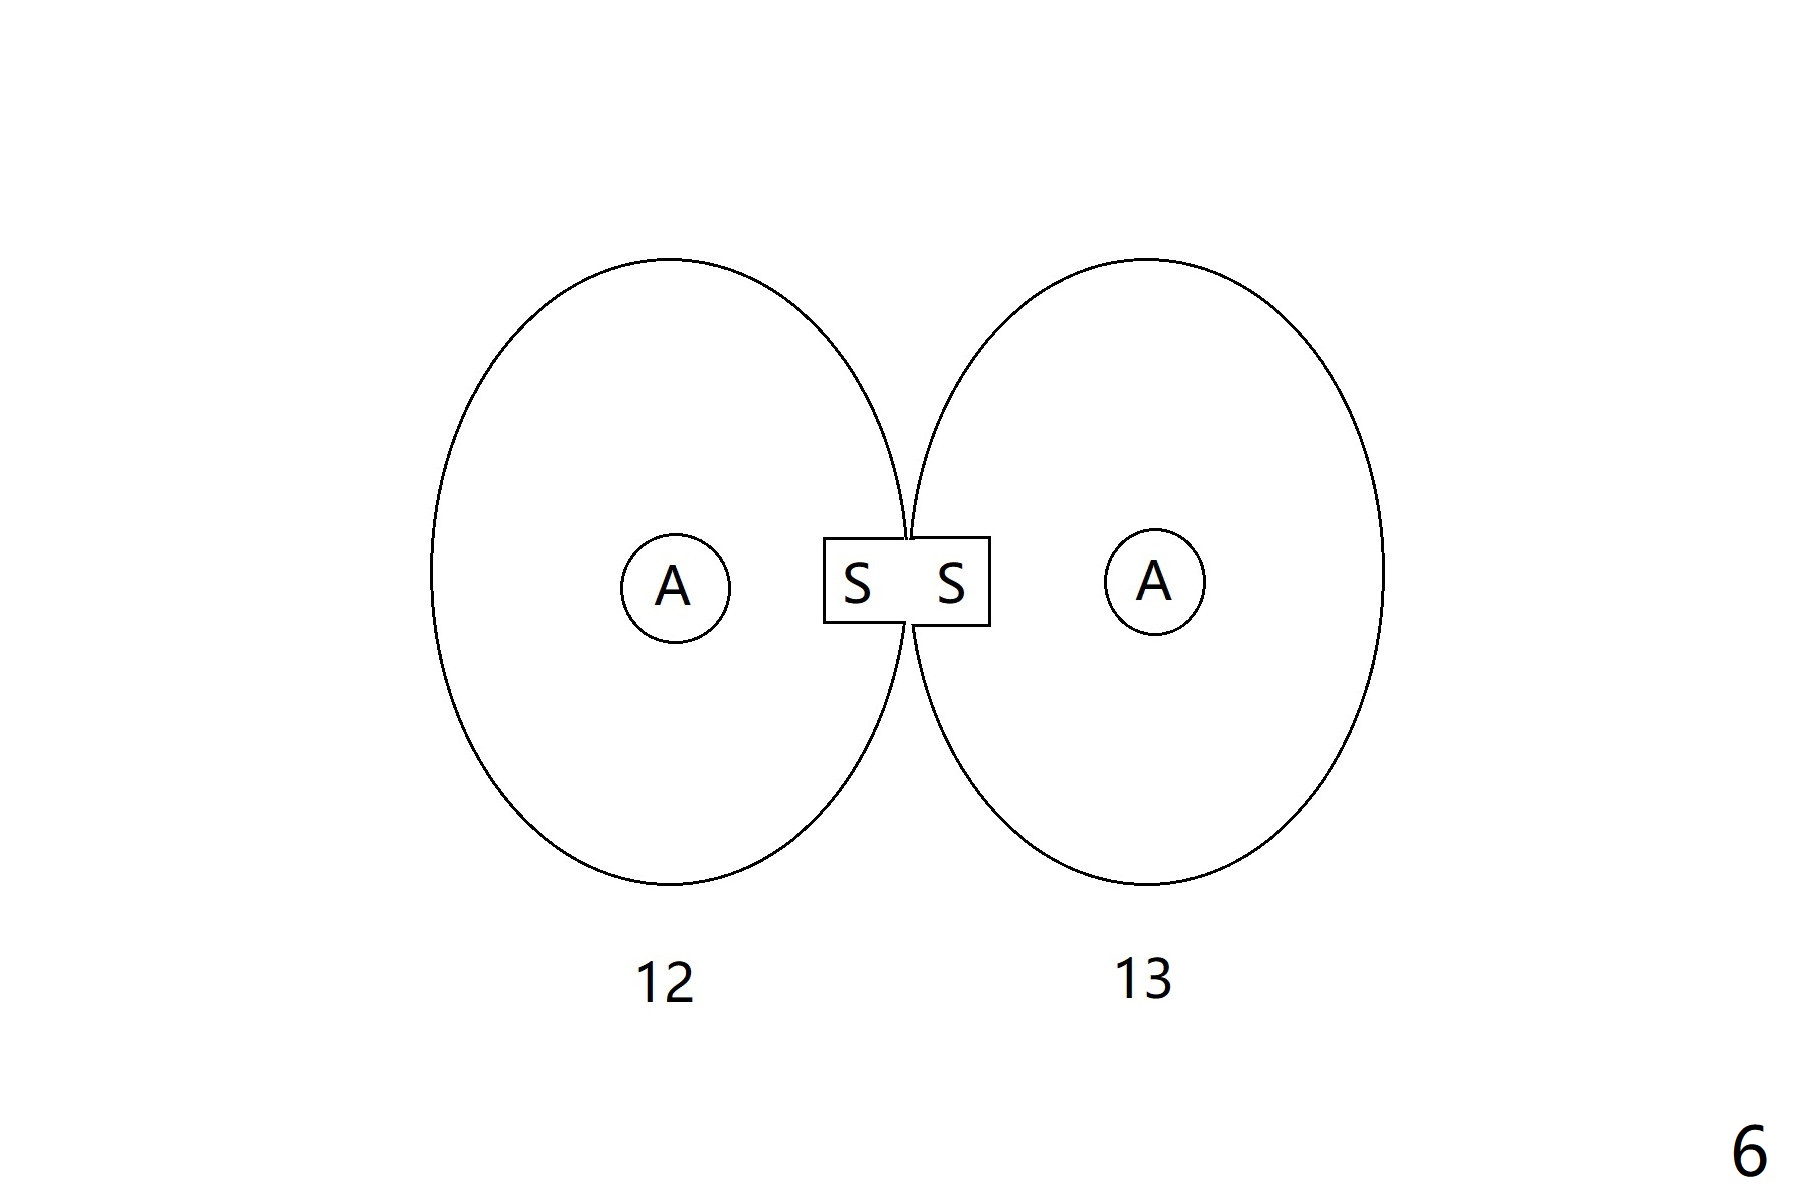

A 66-year-old woman returns to office requesting implant placement at #12 and 13 at an appointment supposed for #5 impression. Depth of osteotomy is 20 mm (gingival level, Fig.1 ( 2mm)). After correction of trajectory at #12 and 3 mm drill for 16 mm at the sites, two of 3.8x16 mm implant are placed with insertion torques of 35 and 15 Ncm, respectively (Fig.2). Before and after change into shorter abutments (4.5x4(4) and (5)), Vera Graft is placed (Fig.3 *). To increase stability, either increase the diameter (4 (Fig.4 at #5) or 4.5 mm instead of 3.8) or length of the implants (red dashed line: sinus floor). Or use dummy implants. The allograft appears to have been incorporated into the host bone nearly 4 months postop (Fig.5). The abutment of the isolate implant at #5 becomes loose twice (Fig.4). To reduce the chance of abutment loosening at #12 and 13, can you make splinted crowns? If the two separate crowns have been fabricated, can you make a slot (with light undercut) in the proximal area of each crown (Fig.6 (occlusal view): S) in addition to access hole (A)? After cementation, composite will be placed in the slots (lock) so that the crowns will not rotate and become loose.